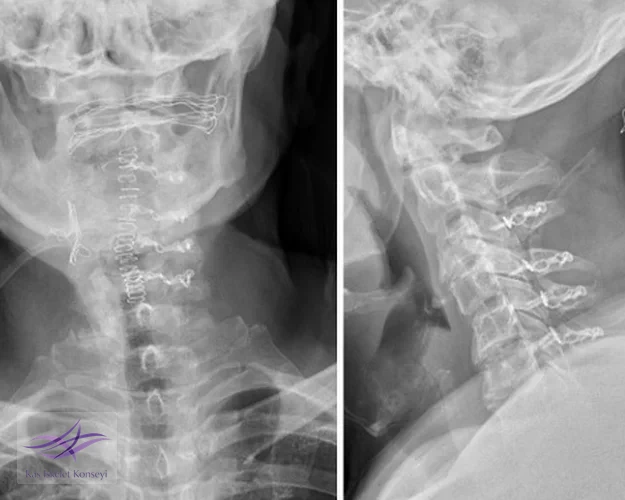

Klinik Seyir: Hastaya cerrahi dekompresyon kararı verildi. C3-C6 seviyelerinde servikal laminoplasti yapıldı. Postop BT incelemelerinde kanal çapının arttığı görüldü. Hastada cerrahiye ait bir komplikasyon olmadı ve klinik durum belirgin düzeldi.

Resim 3. Postop grafide C3-C6 seviyelerinde laminoplasti plakları görülmekte.